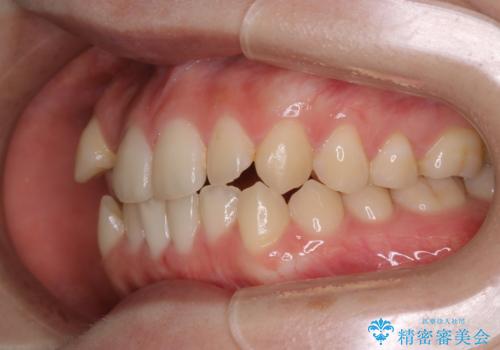

マイクロインプラントを使用して抜歯を回避!八重歯の非抜歯インビザライン治療

- 非抜歯、インビザライン治療希望の患者様です。

右の犬歯が八重歯になっており、通常であれば抜歯を選択する可能性が高くなりますが、

マイクロインプラントを使用することで非抜歯での治療が可能となりました。